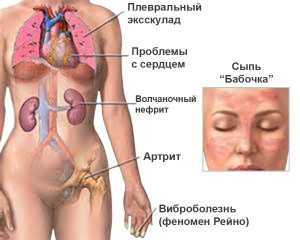

Системная красная волчанка – это хроническое заболевание с множеством симптомов, в основе которого лежит постоянное аутоиммунное воспаление. Чаще болеют молодые девушки и женщины от 15 до 45 лет. Распространенность волчанки: 50 человек на 100 000 населения. Несмотря на то, что недуг встречается довольно редко, знать его симптомы крайне важно. В этой статье расскажем также и о лечении волчанки, которое обычно назначается докторами.

Симптомы системной красной волчанки

Поражение суставов

Артрит наблюдается у 90% больных. Проявляется мигрирующими болями в суставах и поочередным воспалением суставов. Очень редки случаи, когда постоянно болит и воспаляется один и тот же сустав. В основном поражаются межфаланговые, пястно-фаланговые и лучезапястные суставы, реже голеностопные суставы. Крупные суставы (например, коленные и локтевые) страдают значительно реже. Артрит обычно сочетается с сильными болями в мышцах и их воспалением.

Кожный синдром

Наиболее часто встречается типичная волчаночная «бабочка» – покраснение кожи в области скул и спинки носа.

Поражение серозных оболочек

Подобное поражение относится к диагностическим критериям, так как встречается у 90% больных. Сюда относят:

Поражение сердечно-сосудистой системы

Синдром Рейно

Синдром Рейно проявляется спазмом мелких сосудов, что у больных волчанкой может приводить к некрозам кончиков пальцев кистей, тяжелой артериальной гипертензии, поражению сетчатки.

Поражение легких

Поражение почек

Поражение центральной нервной системы

Одно из самых тяжёлых болезней — системная красная волчанка (СКВ). Она характеризуется аутоиммунным воспалением с множеством других симптомов. Это заболевание опасно своими осложнениями. При нём страдают органы многих систем организма, но больше всего проблем происходит с опорно-двигательным аппаратом и почками.

При волчанке поражаются различные системы организма:

- Дыхательная. Лёгочные патологии развиваются в большей половине случаев при СКВ. Чаще всего воспаляется оболочка, покрывающая лёгкие (плеврит). Больного мучают боли в груди и одышка. Может возникнуть волчаночный пневмонит, характеризующийся кашлем с кровянистой мокротой. При лёгочной гипертензии поражаются сосуды лёгких. Также возможна закупорка артерии тромбом (тромбоэмболия).

- Сердечно-сосудистая. Волчанка характеризуется поражением структуры сердца, наружной оболочки, внутреннего слоя, клапанов и коронарных сосудов. Часто возникает перикардит, при котором воспаляются серозные оболочки, поражающие сердечную мышцу. При возникновении миокардита нарушается ритм сердца и передача нервного импульса, а также развивается острая или хроническая недостаточность.

Эту болезнь иначе называют мультисистемным воспалительным заболеванием, поскольку происходит поражение практически всех органов и систем: суставов, кожи, почек, головного мозга и пр.